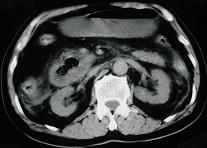

问题 男,78岁,阵发性上腹部疼痛10年伴呕吐,加重1年,影像检查如下图,应诊断为 ( )

选项 A、十二指肠结核 B、肠系膜上动脉压迫综合征 C、十二指肠憩室 D、十二指肠淋巴瘤 E、十二指肠癌

答案 C